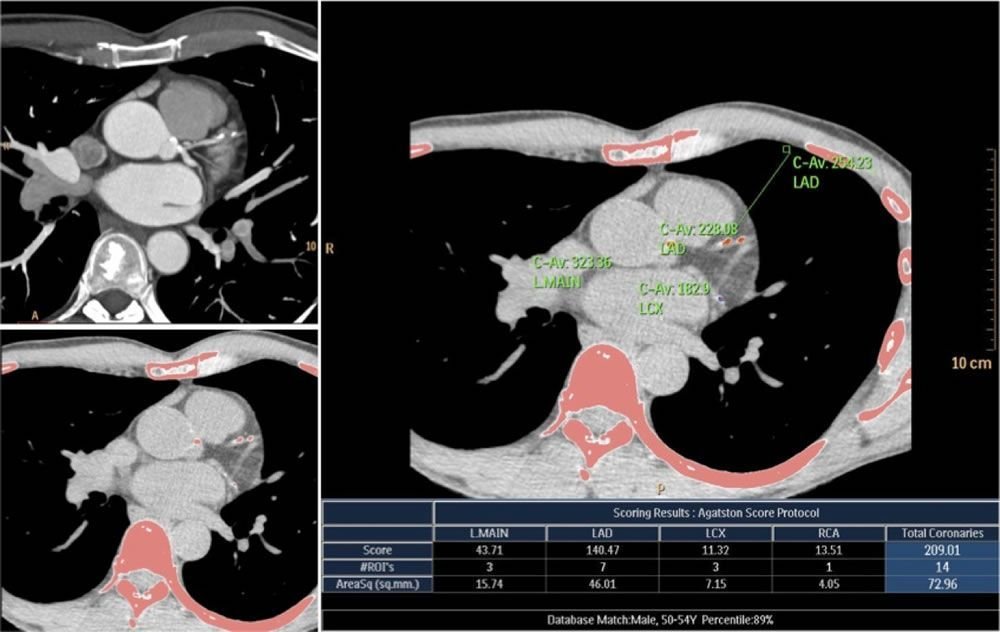

Liderazgo en diagnóstico cardiovascular

Somos referentes en estudios cardiovasculares no invasivos orientados a la detección temprana y evaluación precisa de la enfermedad ateroesclerótica y otras patologías cardíacas. Nuestra tecnología permite un análisis detallado de las arterias coronarias y la función miocárdica.

Angiotomografía Coronaria y Score de Calcio

Evaluación del riesgo cardiovascular y detección de obstrucciones coronarias.